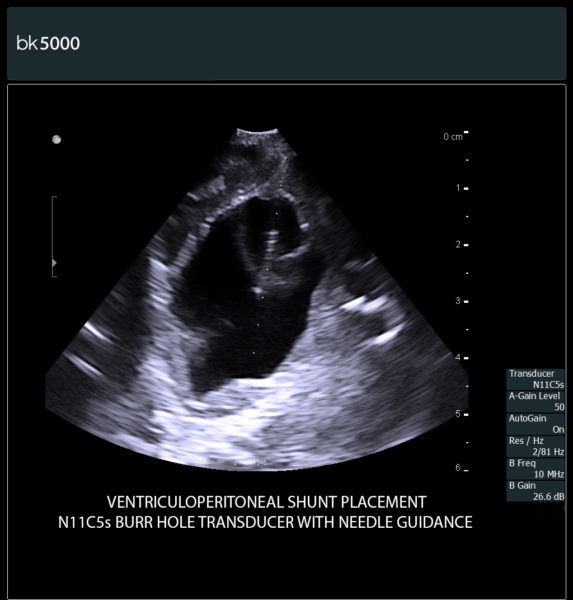

Ultrasound can improve neurosurgical procedures by helping you navigate and identify lesions and anatomical structures in real-time. This is particularly important as the data obtained from a preoperative CT or MRI scan can be outdated at the time of surgery. The bk5000 neurosurgical system provides the highest quality images that allow you to clearly see the margins of a lesion and to determine the best course of action. Using advanced graphics processing technology, this powerful system provides immediate, auto-optimized images that allow you to see the information you need, faster.

Transducers designed for Neurosurgery

The specialized, high-resolution, sterilizable neurosurgery transducers enable you to obtain detailed images of the brain and spinal cord. They have a convenient Smart™ button that lets you activate the transducer, then freeze, store or print the images at the press of a button. Disposable, easy-to-use needle guides assist with targeting lesions.